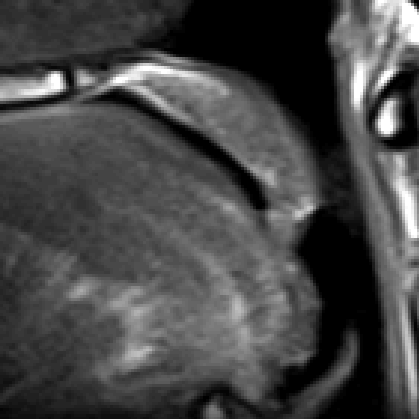

We point out that the noisy image in Fig. 10 is obtained directly by inverse Fourier transform and we can see that the noise level is quite high in this case. Both the PCM-TV and the PCM-TV-TFV are able to produce more reasonable visual results. To see a deep comparison, we zoom in the red square part of Fig. 10 and present the approximation errors in Fig. 11.

Refer to caption

(a) Groud Truth

(b) PCM-TV

(c) PCM-TV-TFV

Figure 11: Zoomed in comparison of the red square in Fig. 10. Figure (a) is the true surface. Figure (b) shows the difference between the truth and the one reconstructed by PCM-TV. Relative error 62%absentpercent62\approx 62\%. Figure (c) shows the difference between the truth and the one reconstructed by PCM-TV-TFV. Relative error 32%absentpercent32\approx 32\%.

We can see that the PCM-TV-TFV has a much less error than the PCM-TV model for the surface reconstruction.